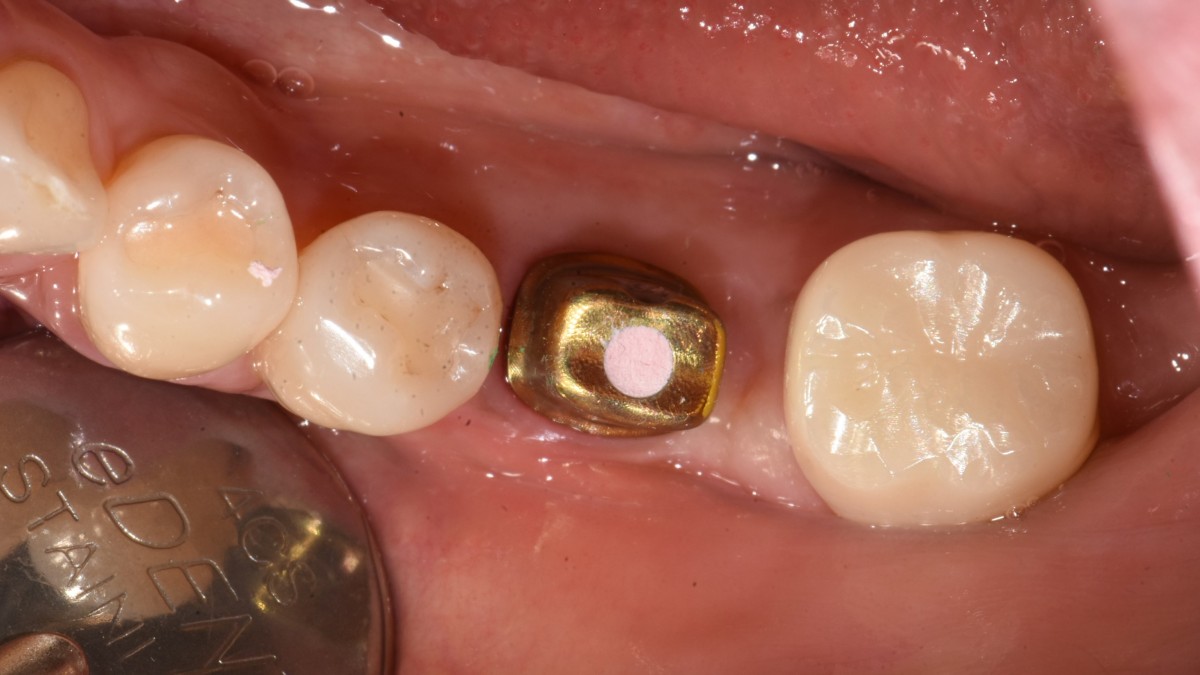

A 51-year-old patient complained of an

old-crowned molar. The lower left molar had a gold crown, and the margin showed discoloration indicative of inner caries. Also, it had furcation-involved periodontitis

with an apical lesion.

Extraction and immediate placement of an implant.